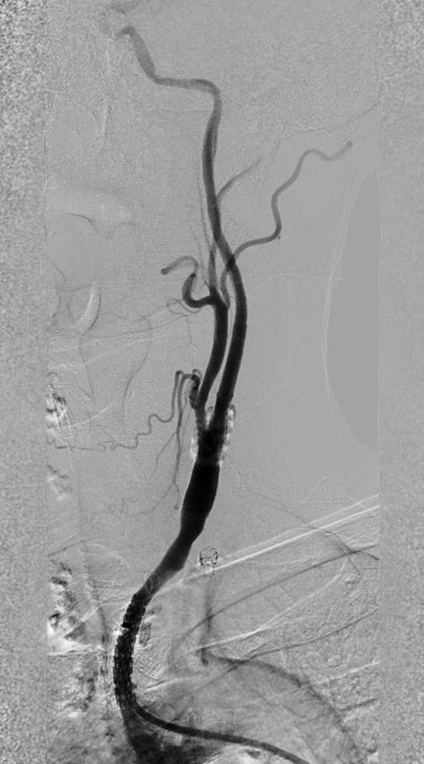

CASE 3:74岁女性,左侧颈动脉重度钙化狭窄,IVL治疗后管腔获得理想,支架置入后残余狭窄低。

左侧颈动脉

重度钙化狭窄

IVL后即刻管腔

获得理想

支架后

残余狭窄低